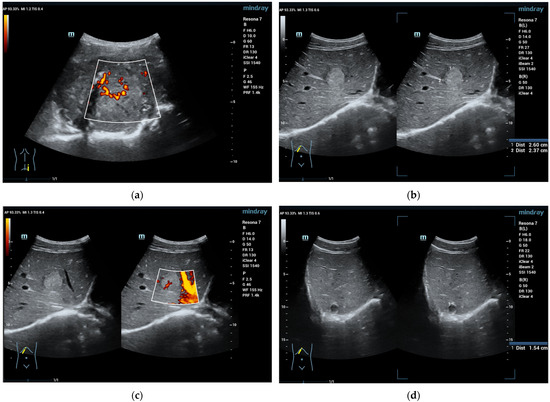

Figure 1.

A 16-year-old boy, athletic, soccer player, complaining of pain in the right lumbar–gluteal region for 10 months. MRI showed a large mass in the right iliac bone with protrusion to the muscles. Biopsy result is Ewing sarcoma. This mass is clearly visible on ultrasound (a). In liver B mode ultrasound revealed several foci: 26 × 23 mm echogenic with some hypoechoic rim (b) and entering vessel on Power Doppler mode (c) and 15 mm hypoechoic cystic-like (d). CEUS exam showed rapid filling (e) with early washout in the middle of the arterial phase (f). Washout progresses in the portal venous (g) and late venous phases (h). Liver metastases of Ewing sarcoma diagnosed. (SC5-1U transducer).